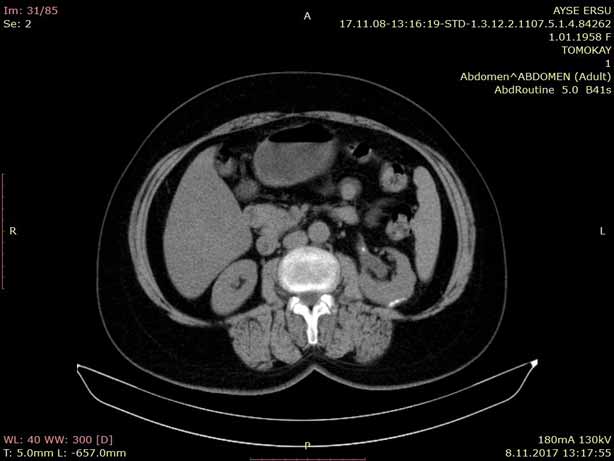

Bursa’da ilaçlı tomografi (kontrastlı BT) çektirmeyi düşünen hastaların en çok merak ettiği

konulardan biri ilaçlı tomografi yan etkileridir. Kontrastlı bilgisayarlı tomografi (BT), damar

yoluyla verilen kontrast madde sayesinde organların, damarların ve dokuların daha net

görüntülenmesini sağlayan ileri bir radyolojik görüntüleme yöntemidir.

Bursa’daki merkezimizde ilaçlı tomografi işlemleri, hasta güvenliği ön planda tutularak

modern BT cihazları ile gerçekleştirilmektedir.

İlaçlı Tomografi (Kontrastlı BT) Nedir?

İlaçlı…